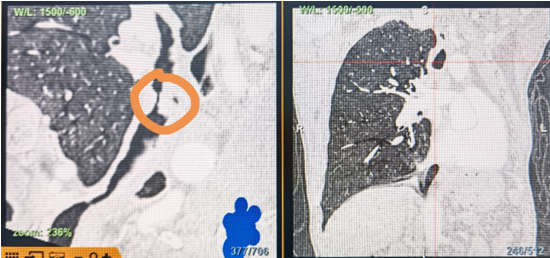

時(shí)間就是生命!了解患者病情后,歐陽(yáng)海峰立刻啟動(dòng)氣道梗阻緊急救治通道,協(xié)調(diào)院前轉(zhuǎn)運(yùn),急診快速入院流程。凌晨患者入院胸部CT顯示,現(xiàn)存唯一的呼吸通道在右主支氣管處,狹窄處僅約3毫米,患者命懸一線!

運(yùn)用呼吸介入技術(shù),軟硬鏡結(jié)合快速開(kāi)通氣道,是患者目前唯一可行的治療方案,手術(shù)刻不容緩!但存在麻醉后氣道完全塌陷閉合、大出血、窒息等巨大風(fēng)險(xiǎn)?;颊叽饲敖舆B轉(zhuǎn)診3家醫(yī)院,均建議保守支持治療或轉(zhuǎn)院。歐陽(yáng)海峰詳細(xì)了解患者病史,全面評(píng)估影像檢查結(jié)果后,決定盡快進(jìn)行手術(shù),組織醫(yī)護(hù)團(tuán)隊(duì)對(duì)患者進(jìn)行持續(xù)密切監(jiān)測(cè),充分保障其術(shù)前安全。